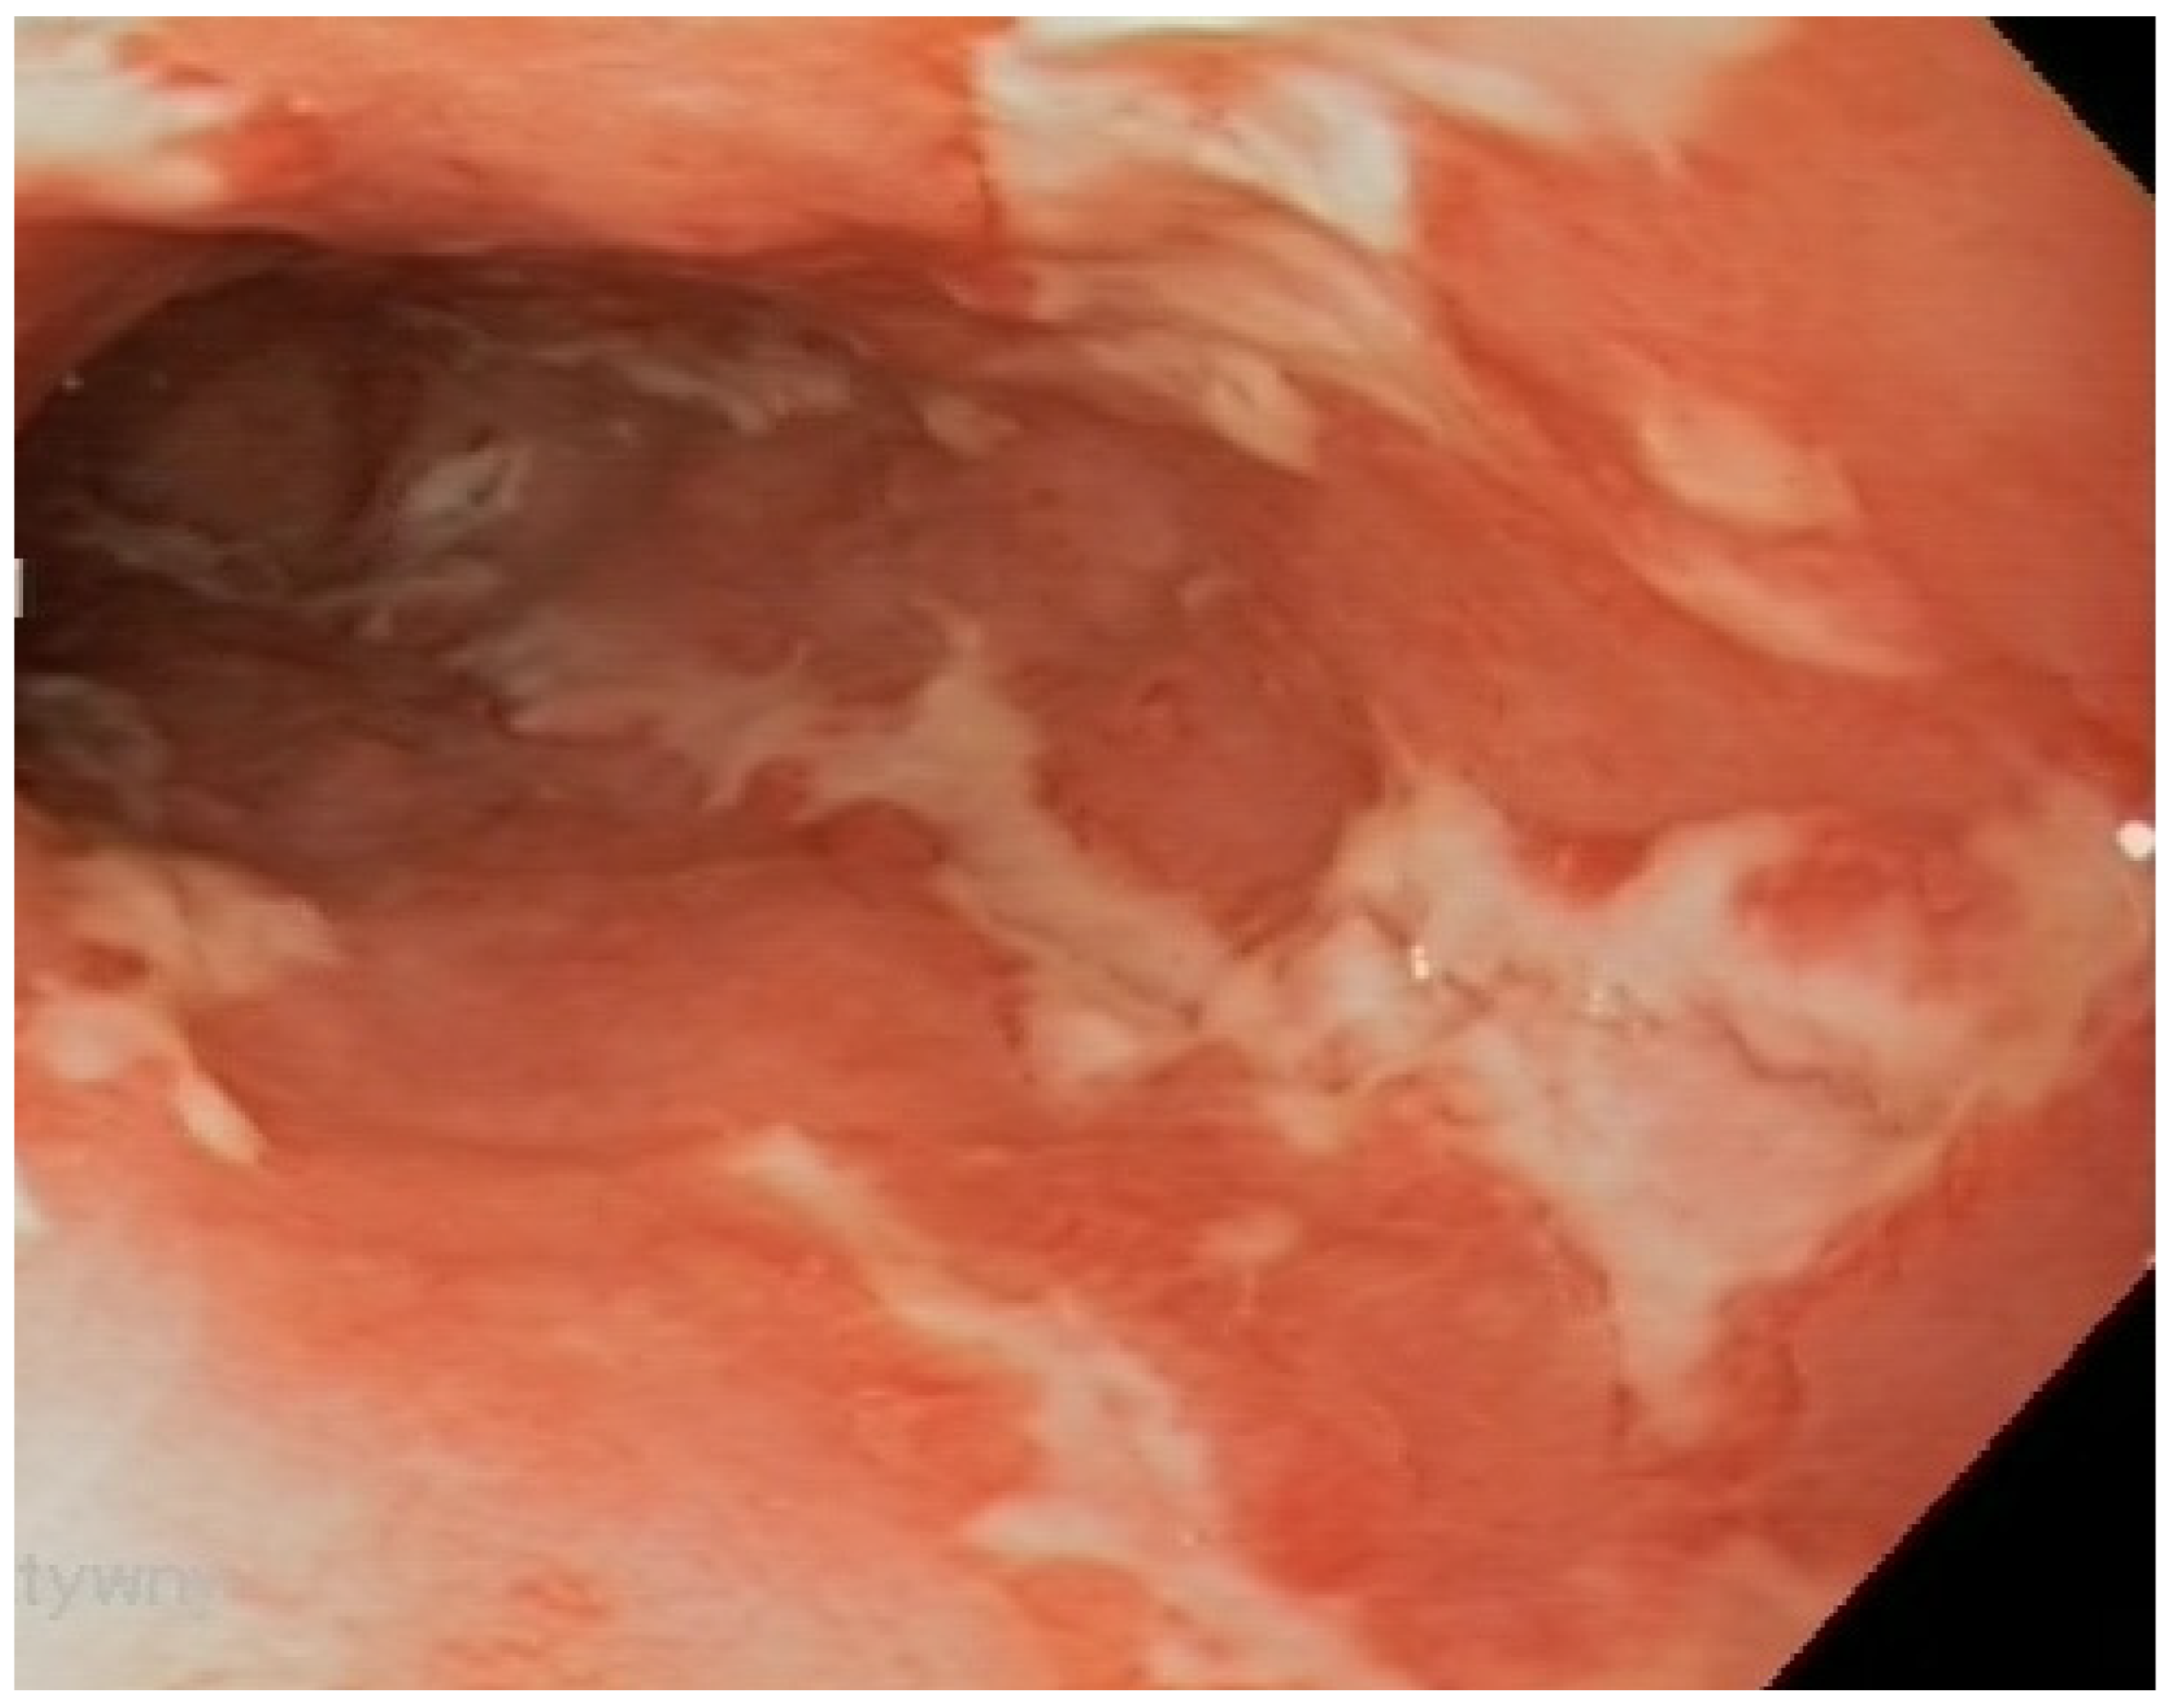

Figure 4.

Mucositis in the distal segment of the ileum, with ulcers in a patient with Crohn’s disease.